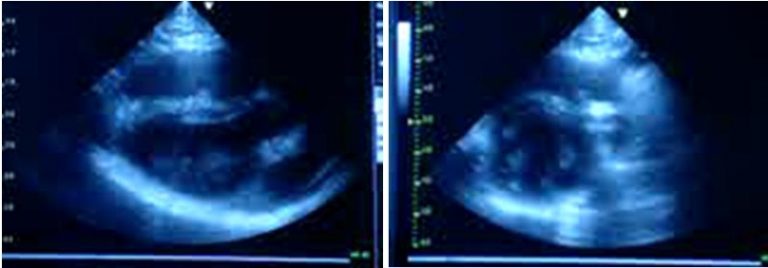

Nach adenoviralem oder AAV-vermittelten Gentransfer wurden bei chronischer Herzmuskelschwäche relevante Proteine direkt in Kaninchenherzen in vivo exprimiert, die an dilatativer Kardiomyopathie erkrankt waren. Die Methode erfordert keine zeitaufwändige Generation von transgenen Mauslinien und keine Kreuzungsversuche.

Der Effekt auf die krankheitsrelevanten Parameter wurde mittels Echokardiographie und intrakardialen Hämodynamik-Messungen ermittelt (Methode beschrieben in: Weig HJ, Laugwitz KL, Moretti A, Kronsbein K, Städele C, Brüning S, Seyfarth M, Brill T, Schömig A, Ungerer M. Enhanced cardiac contractility after gene transfer of V2 vasopressin receptors in vivo by ultrasound-guided injection or transcoronary delivery. Circulation. 2000; 101(13):1578-85.)

Unter einer Vielzahl von untersuchten Zielproteinen wurden dabei einige besonders relevante identifiziert. In der Abbildung sind Ergebnisse zu verschiedenen Proteinen aufgeführt, deren Aktivierung (grün markiert) oder deren Hemmung (rot markiert) direkt einen positiven Effekt auf die Herzmuskelkraft und den Krankheitsverlauf der Herzinsuffizienz hatte. Diese Proteine gehören zu den Familien der aktivierenden Rezeptoren, der Calcium-regulierenden Proteine, der Apoptose (Zelltod)-regulierenden Proteine, oder der kontraktilen Proteine. Weitere Arbeiten zeigten, dass Wirkstoffe, die an diese Proteine binden, eine noch effektivere Behandlung von Patienten mit Herzinsuffizienz ermöglichen könnten.